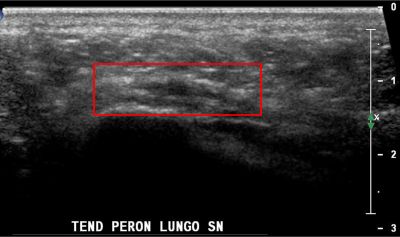

Tendinopatia del muscolo peroneo lungo tendine del m. peroneo lungo